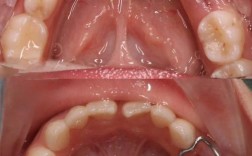

| 口腔局部评估 | CBCT/全景片(测量骨高度、厚度、密度)、牙周检查(探诊出血、牙周袋深度) | 评估骨量是否充足、有无牙周炎等基础疾病 |

| 口腔黏膜检查 | 观察有无溃疡、白斑、红斑,唾液分泌量(如Schirmer试验) | 确认黏膜愈合情况,排除活动性病变 |

- 术后密切随访:术后1周、1个月、3个月复查,观察伤口愈合、种植体稳定性及有无感染迹象,定期监测血常规。